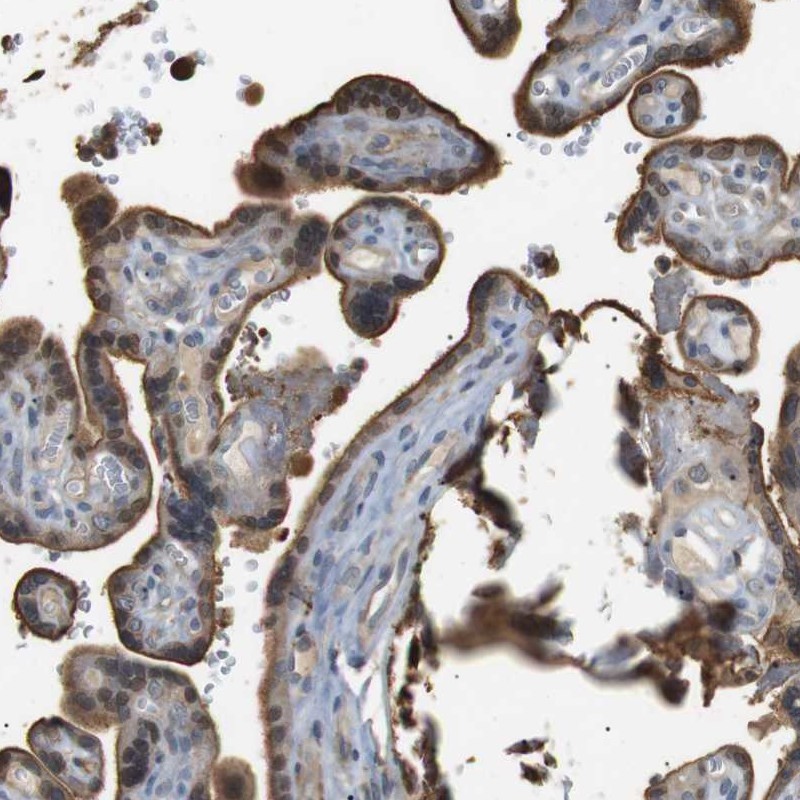

Immunohistochemistry analysis in human placenta and stomach tissues using Anti-P2RY1 antibody. Corresponding P2RY1 RNA-seq data are presented for the same tissues.